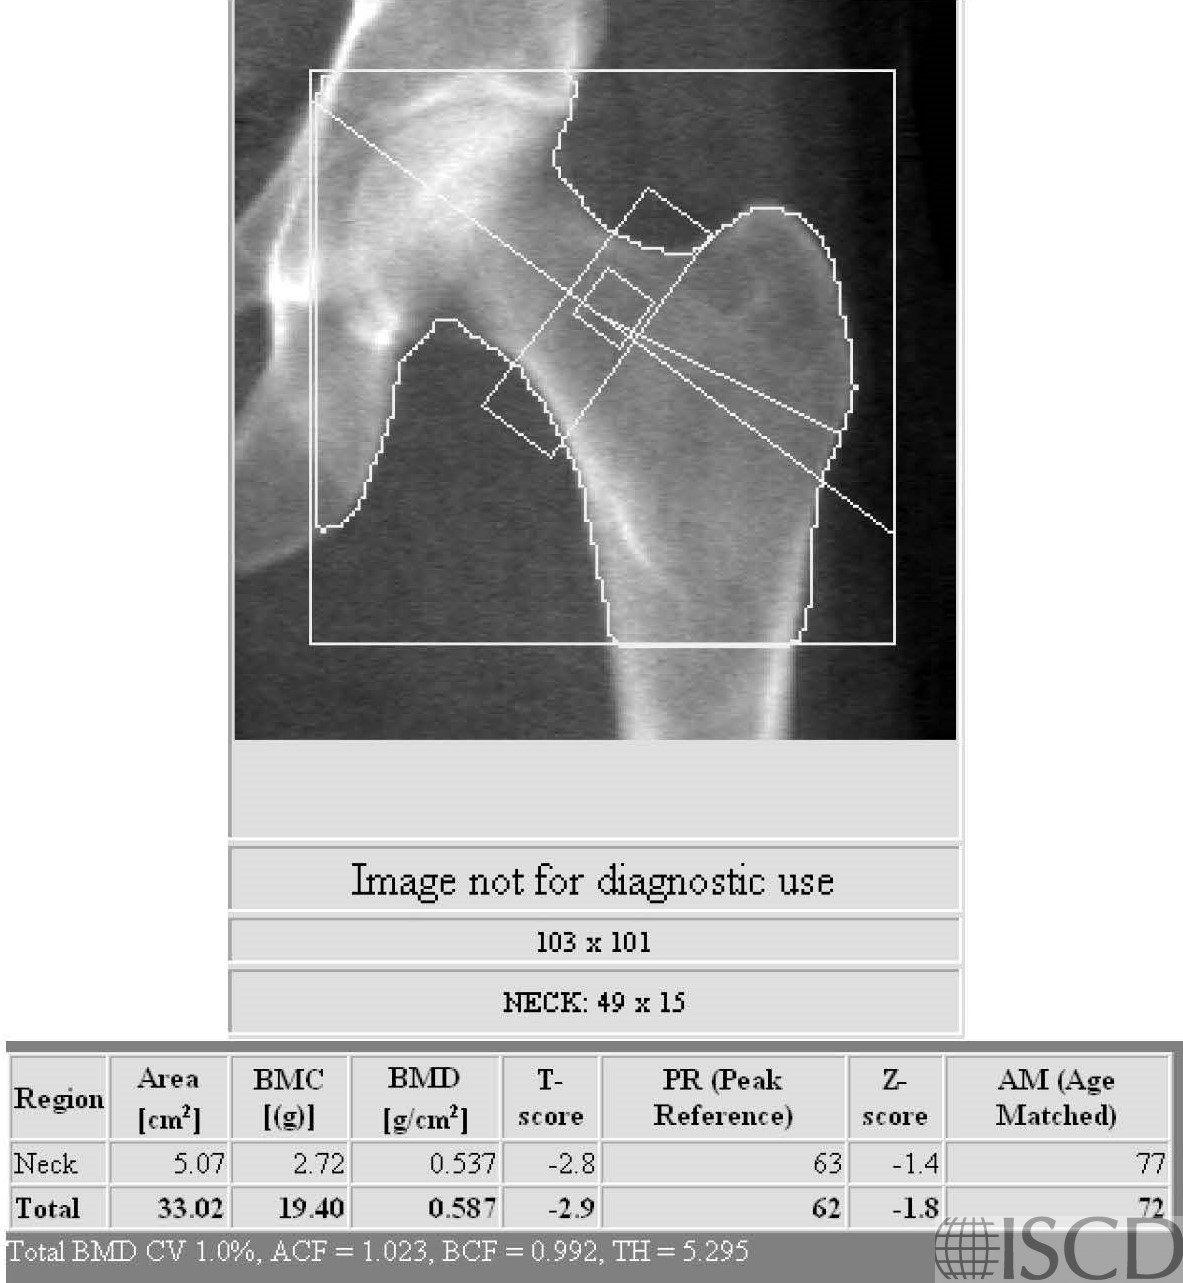

This is the left proximal femur Hologic DXA scan from a woman with biopsy-proven celiac disease.

This is a DXA scan from a 65-year-old Caucasian female referred with low bone mineral density and a poorly healing fracture. The second cause work up demonstrated celiac sprue with anti-TTG > 150. The diagnosis was subsequently confirmed on a small bowel biopsy. There are no specific DXA finding that would suggest celiac sprue over another secondary cause. A thoughtful secondary cause work up is important in patients being evaluated for low bone mineral density and fracture. Relatively large increases in bone mineral density have been reported with the treatment of celiac sprue with a gluten-free diet.